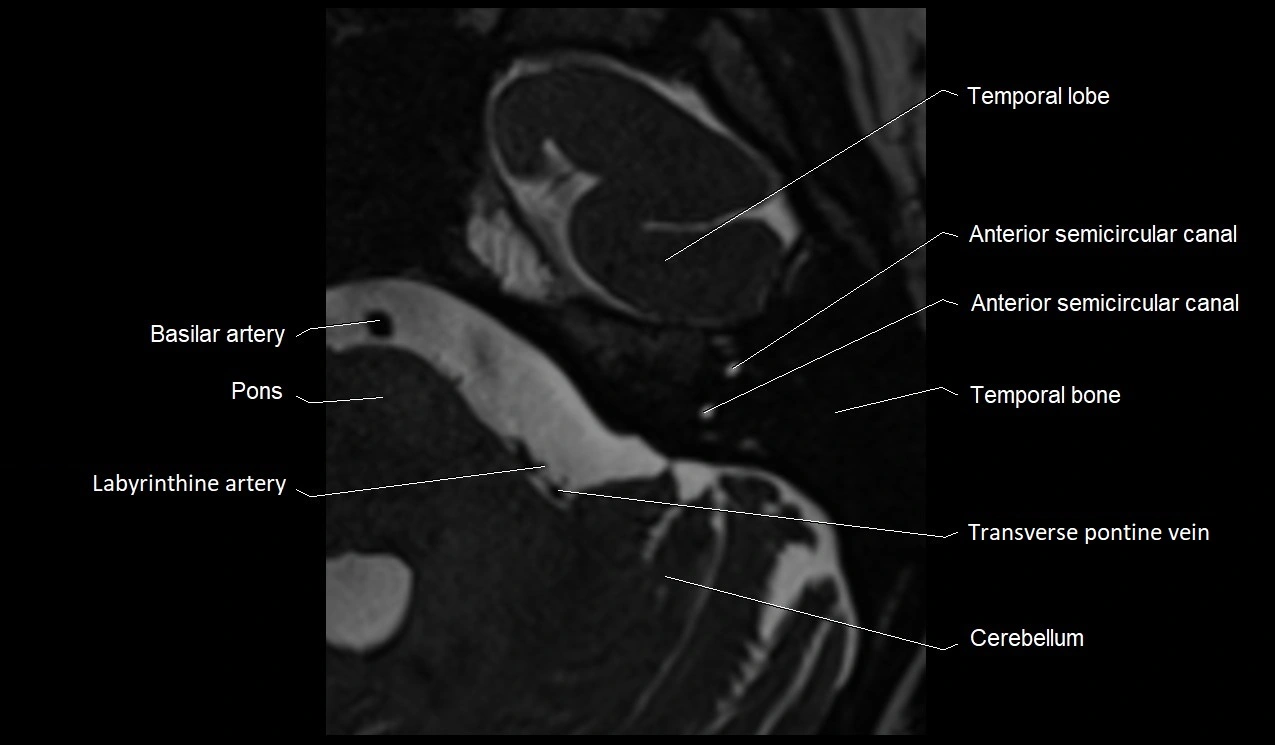

MRI images

image